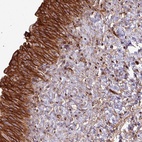

Immunohistochemical staining of human urinary bladder shows strong cytoplasmic and membranous positivity in urothelial cells.